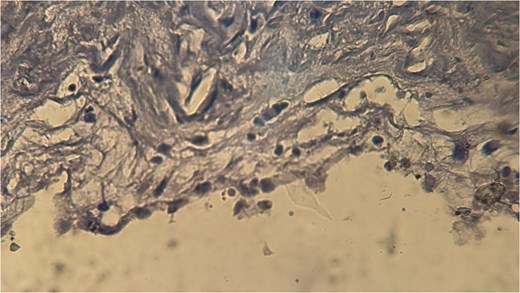

A 60-year-old Moroccan female with no significant medical history presented with chronic periumbilical pain lasting several months, without associated digestive or systemic symptoms, and preserved general condition. Clinical examination revealed periumbilical tenderness. Abdominal ultrasound was unremarkable, prompting an abdominopelvic CT scan, which identified a retroperitoneal inter-aortocaval cystic lesion measuring 86 mm. Surgical exploration revealed a large cystic mass in the mesentery of the small intestine, which was entirely excised. Histopathological examination showed variable-sized cystic cavities with a lymphatic appearance (Fig. 1), lined by flattened and regular endothelium. Some cavities contained pale eosinophilic material interspersed with lymphocytes and areas of red blood cells (Fig. 2). The interstitial tissue exhibited lymphocytic and plasmacytic inflammatory infiltrates. Immunohistochemistry confirmed the lymphatic nature with positivity for Podoplanin/D2–40 (Fig. 3) and CD34 (Fig. 4) and negativity for calretinin (Fig. 5). The patient’s postoperative course was uneventful.

Histopathological examination showing cystic cavities of varying sizes lined by flattened endothelium.